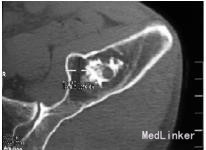

查体:左侧髋关节“4”字实验完成较右侧差,左下肢直腿抬高实验30°。 辅查:腰椎CT:L4/5、L5/S1腰椎间盘突出并左侧隐窝狭窄,相应神经根受压,行髋部X线检查提示左髂骨内占位,进一步行骨盆CT检查提示:左髂骨内可见1大小约4cm×3cm近椭圆形占位性病变,边界清楚,周围骨组织可见厚薄不一的硬化边,其中央有钙化表现,未见骨膜反应,测CT值在-118HU~-129HU之间

诊断:(1)左髂骨占位,脂肪瘤待查;内生软骨瘤待查。(2)腰椎间盘突出症(L 4/5、L5/S1)。 治疗:手术剔除。术中所见:左髂骨内可见1大小约4cm×3cm黄色软组织肿块,表面柔软,边界清楚,肿瘤内可见纤维间隔,中央部分不均匀钙化,与周围骨组织无浸润、骨质无破坏表现,术中诊断左髂骨内脂肪瘤。